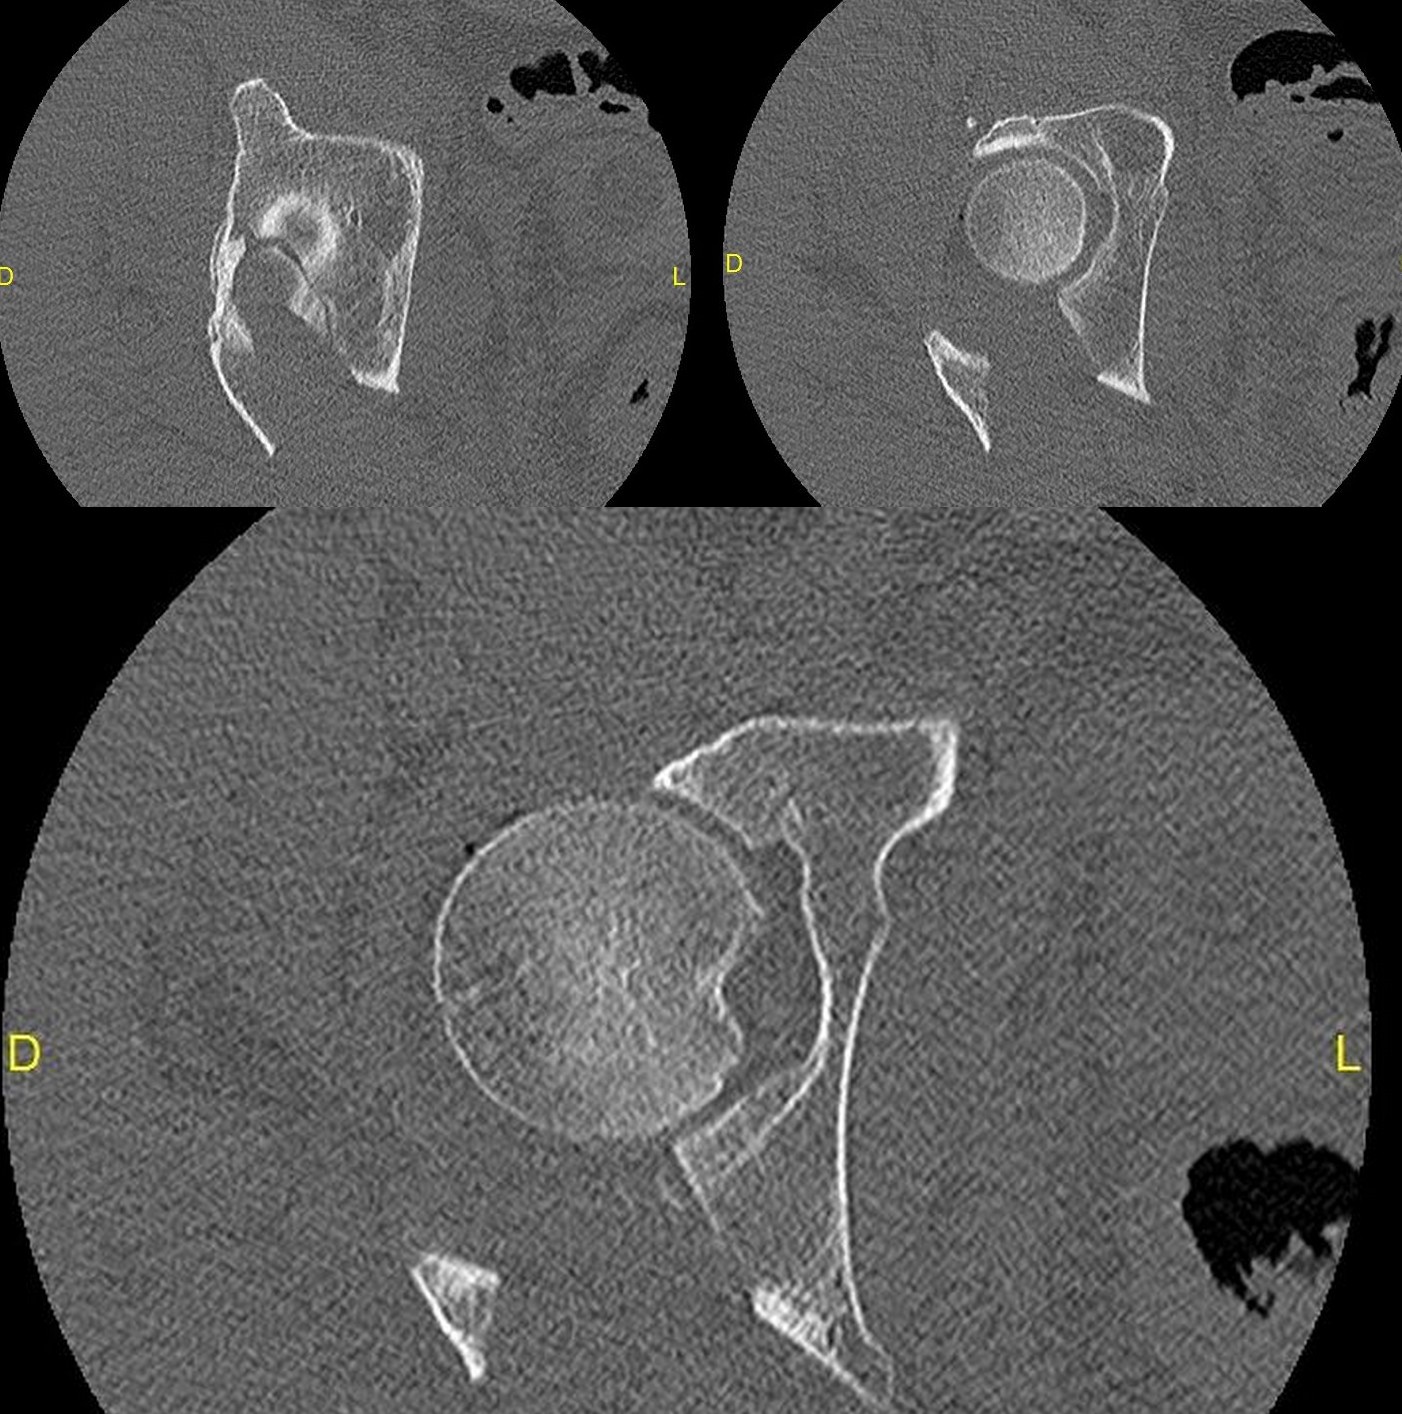

Les fractures du cotyle sont définies comme une solution de continuité du bassin touchant la région cotyloïdienne, ils sont articulaires et nécessitent une réduction parfaite pour éviter la complication la plus évidente et la plus invalidante qui est la coxarthrose [10].

Fractures du cotyle. Diverses fractures du cotyle peuvent survenir, entraînant une atteinte importante de l'articulation de la hanche. L'incidence de ce type de fracture est estimée à.

Fracture du cotyle. La cotyle est la cavité, côté bassin, de l'articulation de la hanche. La fracture du cotyle survient suite à un traumatisme important (accident de la route, chute d'une hauteur élevée). Lorsque la fracture est non déplacée il convient de maintenir une décharge (marche sans appui) pendant 6 semaines.